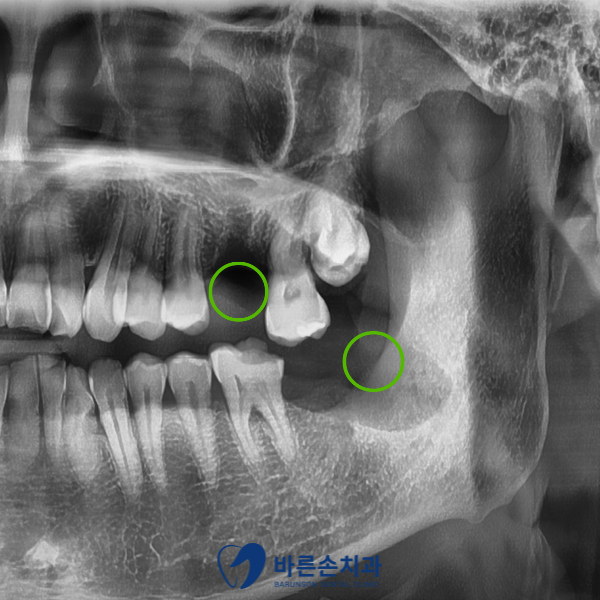

위 사진은 크랙, 염증으로 인해 발치가 필요했던 치아를 모두 발치한 후 파노라마 사진이고

초록색 원 부위에는 추후 임플란트 및 뼈이식을 진행할 계획입니다

위에는 바로 임플란트를 식립하였습니다.

아래는 소량의 뼈 이식 후 기다리기로 합니다.